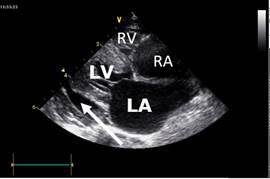

24 hours later he is much more stable

An echocardiogram was performed

Comment on the principle features evident on the echo, in particular the relative sizes of the cardiac chambers and the thickness of the ventricular walls.

Do you know how these images might be generated?